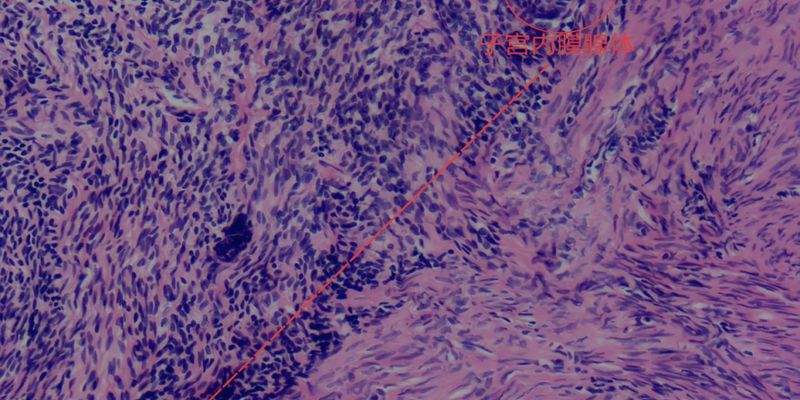

Ozuriftamab Vedotin(Oz-V)是一种条件性可逆活性ADC,其独特之处在于能够特异性靶向ROR2。ROR2是一种跨膜酪氨酸激酶受体,在包括头颈部癌症在内的多种实体瘤中均有表达。值得注意的是,ROR2的过表达常由人乳头瘤病毒(HPV)感染相关的E6/E7癌蛋白驱动,并与不良预后以及对化疗和免疫疗法的耐药性密切相关。通过精准靶向ROR2,Oz-V旨在为传统疗法效果不佳的患者提供更有效的治疗方案。